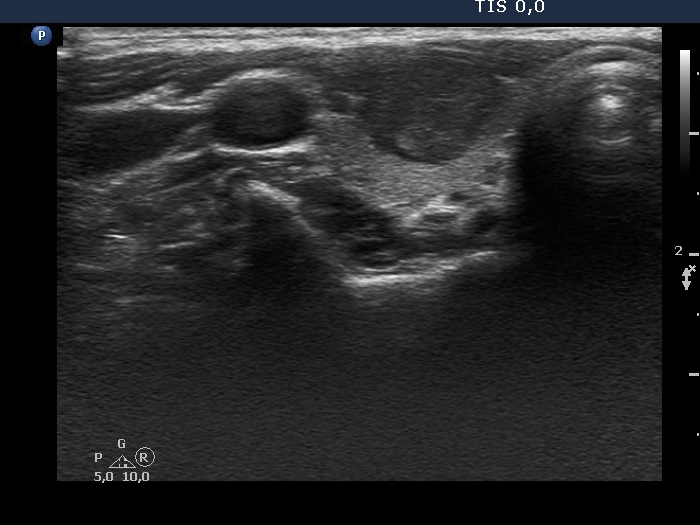

First examination (first row of images)

Clinical data: A 21-year-old woman was referred for evaluation on a nodular goiter. She has noticed an enlargement in the left lobe for a year. On evaluation in another institute, a cystic nodule was diagnosed with a 26 mm maximal diameter and 3 mL brown fluid was aspirated. Cytology resulted in benign cystic lesion.

Palpation: The right lobe was suspicious having a nodule.

Laboratory test: TSH 2.21 mIU/L.

Ultrasonography. The thyroid was echonormal and presented a moderately hypoechoic nodule in the right lobe and a cystic nodule with minimally hypoechoic solid part corresponding to the previously aspirated cystic lesion. The largest diameter of the latter was 11 mm which means that cyst has not refilled. The nodule in the right lobe showed irregular, more hypoechoic areas all along at the periphery. This pattern mimicked halo sign, but indeed the lesion did not have a real halo. The vascularization of the nodule in the right lobe presented an irregularly increased intranodular blood flow while the lesion in the left lobe did signs of perinodular vascularization.

Cytology was performed form the lesion in the right lobe and resulted in follicular proliferation.

Combined ultrasound-cytological diagnosis was benign follicular proliferation.

Suggestion: ultrasound in a year.